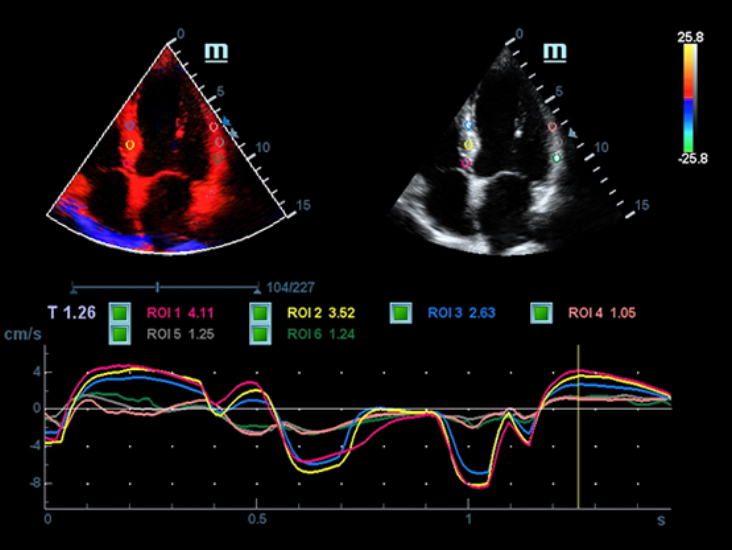

Klinische Bilder